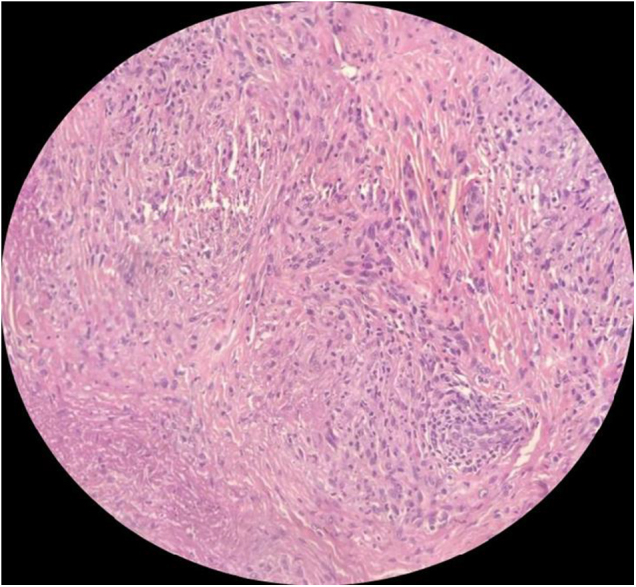

Case presentation: We report the case of a healthy teenager presenting with bilateral subcutaneous nodules on both the palmar and dorsal surfaces of the hands. Histopathological examination confirmed the diagnosis of SGA. Given the patient's aesthetic concerns, a treatment regimen of intralesional corticosteroid injections was initiated, leading to complete resolution of the lesions without recurrence during follow-up.